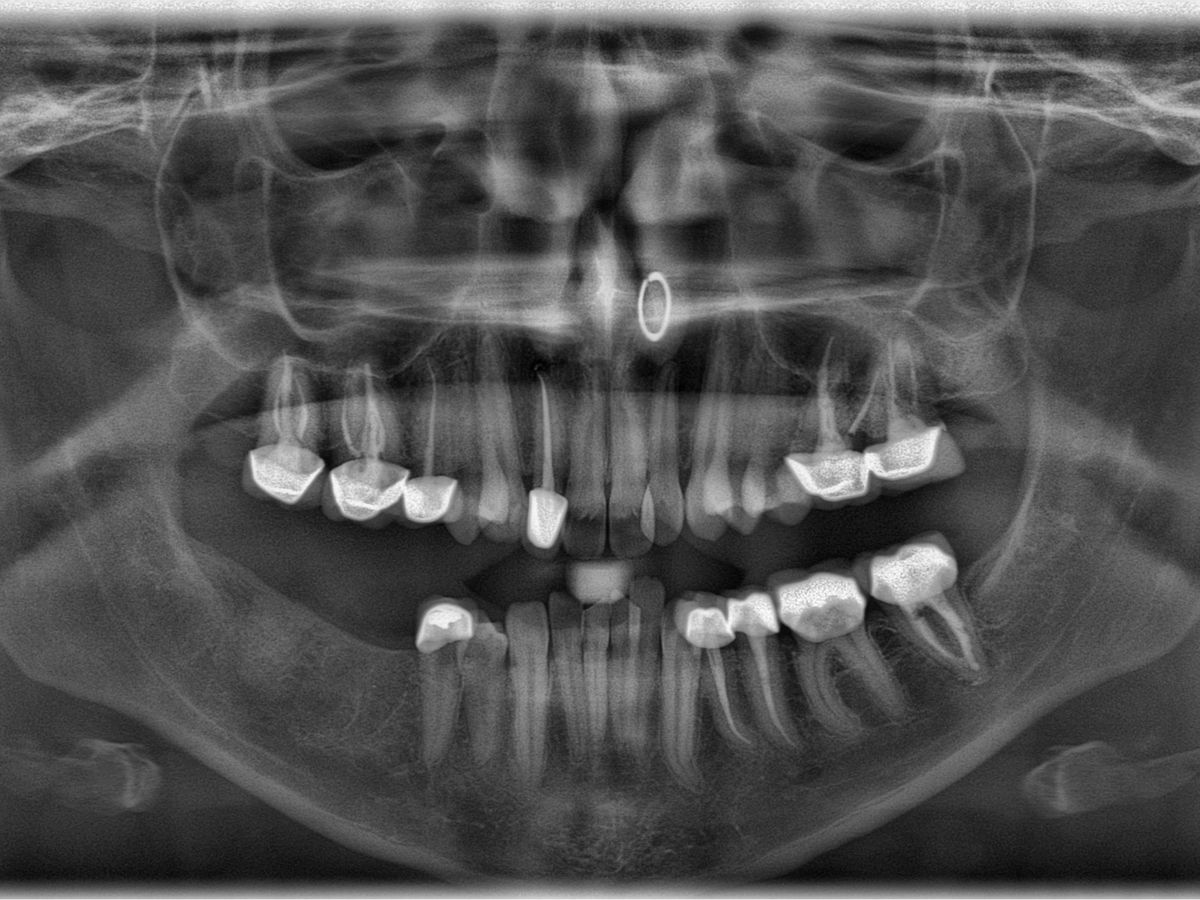

Those of you who know me know I’ve had a lot of dental procedures throughout my life. These procedures have ranged in severity—cavities turned root canals, root canals turned extractions, and so on. If you know me, you might know I am missing two molars on the right side of my bottom teeth; I haven’t chewed on that side in years. Almost all of my remaining molars have had root canals performed on them and have crowns.

To my incredible dismay, as of last month (January), I received a new diagnosis, and a new bill. I have two upper right molars that have root canals that have seemingly failed. They require what is called a retreatment—as the name aptly suggests, they re-treat the tooth, essentially performing another root canal to clean out the present infection. (This also means those glittering porcelain crowns I paid for by myself however many years ago will need to be replaced with new, equally as expensive crowns). I should note: these kinds of dental procedures, especially those in the upper region, are an urgent matter, as the infection is liable to spread if left untreated.